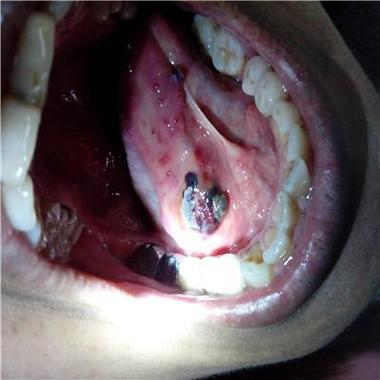

口腔毛细血管充血图片,预示哪些健康问题?

口腔毛细血管充血的典型视觉描述

口腔毛细血管充血,在医学上通常表现为黏膜发红,具体的样子取决于充血的严重程度和原因:

- 点状或条状出血:在红色的背景上,可以看到针尖大小的红色或紫色小点(瘀点),或者细长的线条状出血(瘀斑),这些是毛细血管破裂出血的表现。

- 牙龈肿胀:牙龈不仅红肿,而且看起来肥大,质地松软,一碰就容易出血。